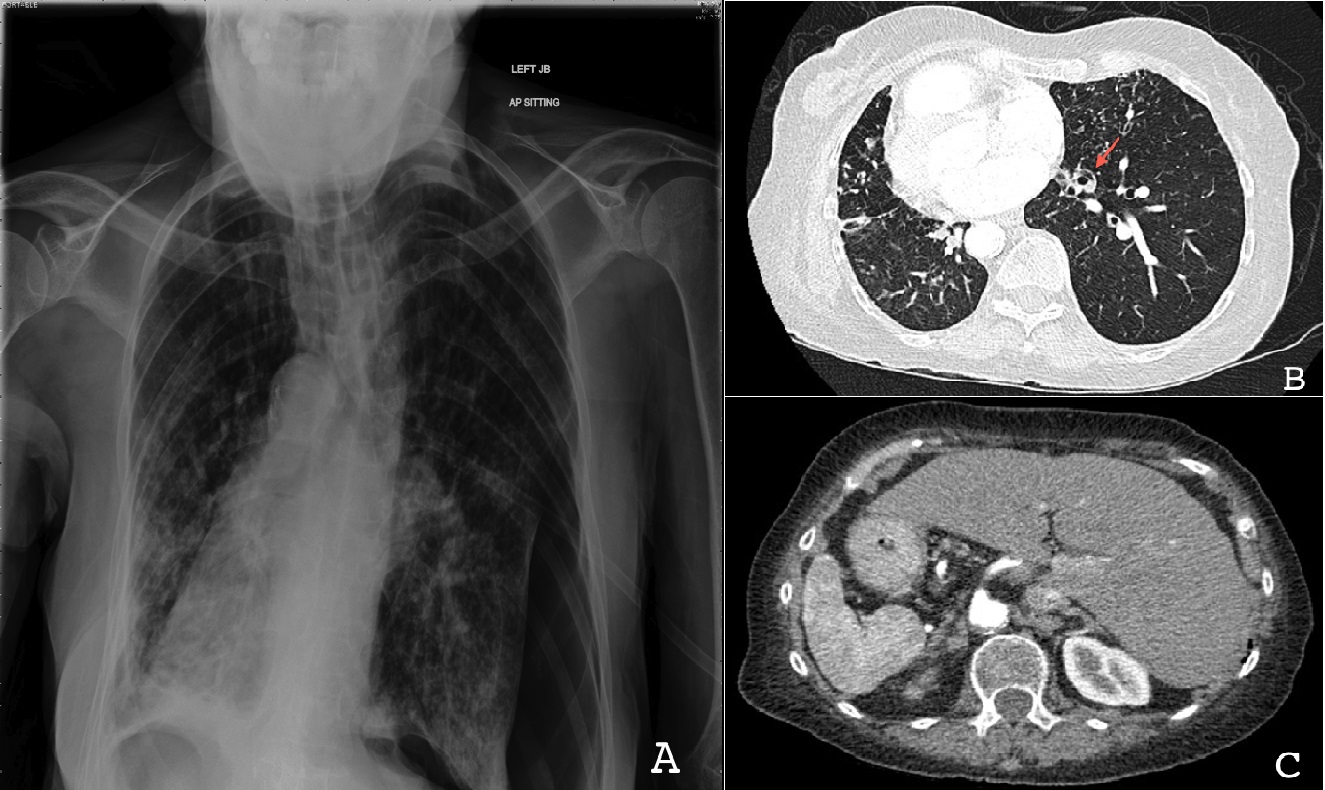

Пороки бронхолегочной системы

Пороки бронхолегочной системы 116 фото